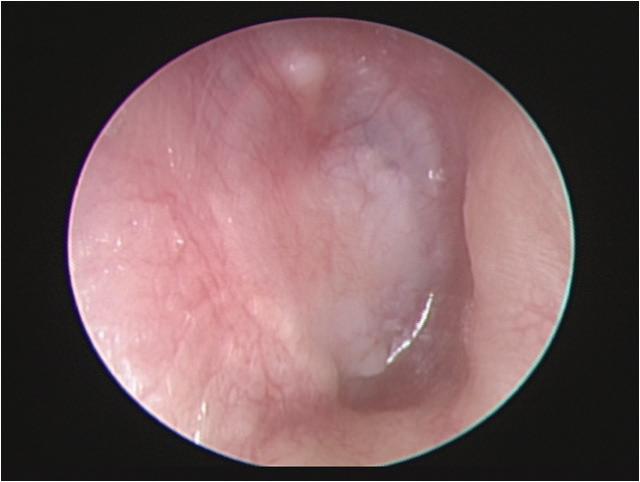

with a temporalis fascia graft and cartilage reinforcement was performed (figure 1). No patient underwent simultaneous ossiculoplasty.

Surgery was considered successful if no residual perforation of the eardrum was present. Postoperative pure-tone audiometry was measured 3 months after surgery. The average hearing level was defined as the mean air-conduction threshold at 500, 1,000, 2,000, and 4,000 Hz.

Results

A total of 30 patients (17 men and 13 women) (32 ears) with a mean age of 52 years (range: 20 to 74) were enrolled. The mean number of previous tympanoplasties was 1.18 (range: 1 to 3); perforation size was small in 14 (43.8%) ears, medium in 13 (40.6%) ears, and large in 5 (15.6%) ears, and included 2 total perforations. The average preoperative air-bone gap was 19.4 ± 7.6 dB. The mean follow-up time was 7 months (range: 1 to 45), and the overall surgical success rate was 93.3%. An image obtained 9 months postoperatively is shown in figure 2.

Figure 2. In this image, an intact eardrum without residual perforation can be seen on otoscopy 9 months postoperatively. Figure 1. These photographs show elements of the single endaural incision approach. A: An endaural incision is made. B: Both the temporalis fascia (dashed arrow) and tragal cartilage (arrow) grafts are harvested with a single incision.